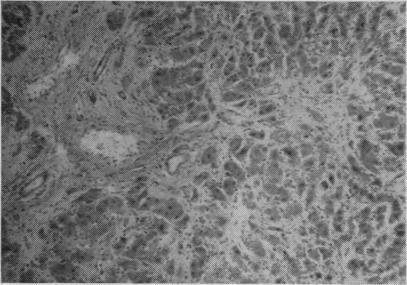

Case report. Ragwort toxicosis in a heifer.

Can Vet J. 1969 Nov;10(11):302-6.

Development of hepatic lesions in calves fed with ragwort (Senecio jacobea).